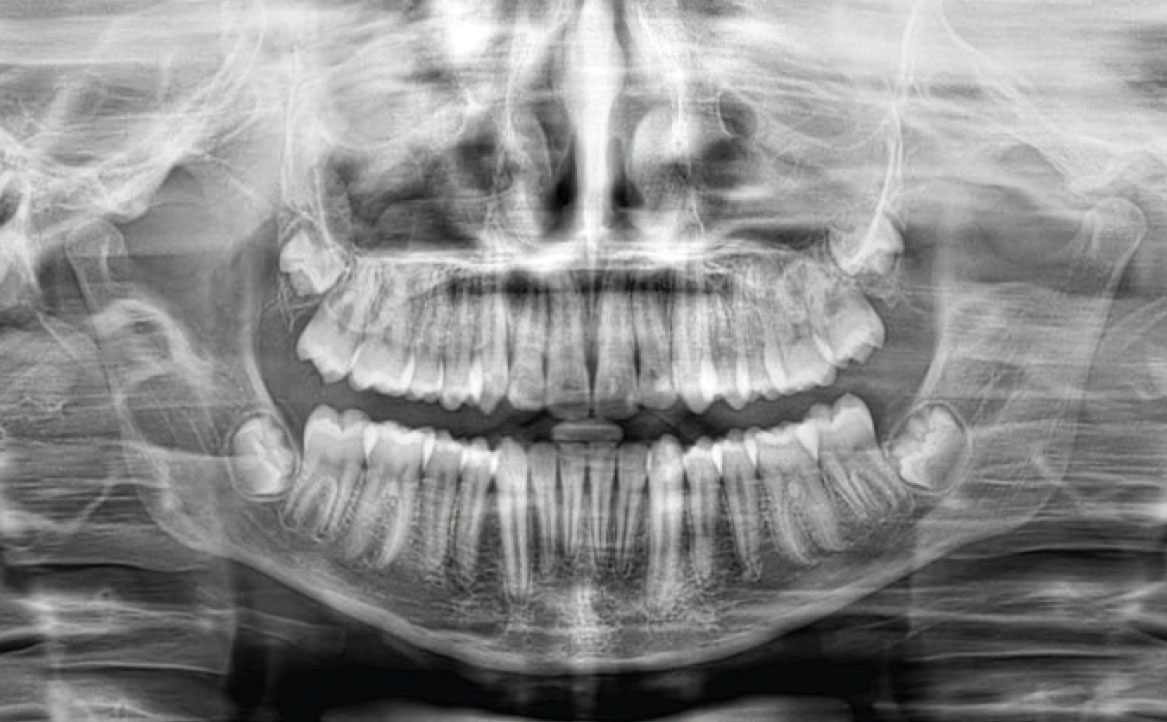

Tale affermazione è stata dimostrata dall’analisi dell’ortopantomografia, in cui era evidente la presenza di materiale non riassorbile, presumibilmente materiale di otturazioni canalari per elementi definitivi, utilizzato in questo caso clinico in elementi dentali decidui, con conseguente difficoltà nel processo di esfoliazione e riassorbimento delle radici stesse (fig. 1).

Terminata la prima fase, all’età di 11 anni, il paziente è stato rivalutato tramite gli esami radiografici. Dall’OPT si osservava la presenza della dentatura permanente, con prossima esfoliazione dei settimi, oltre alla formazione delle gemme degli elementi 18-28-38-48 (fig. 4).